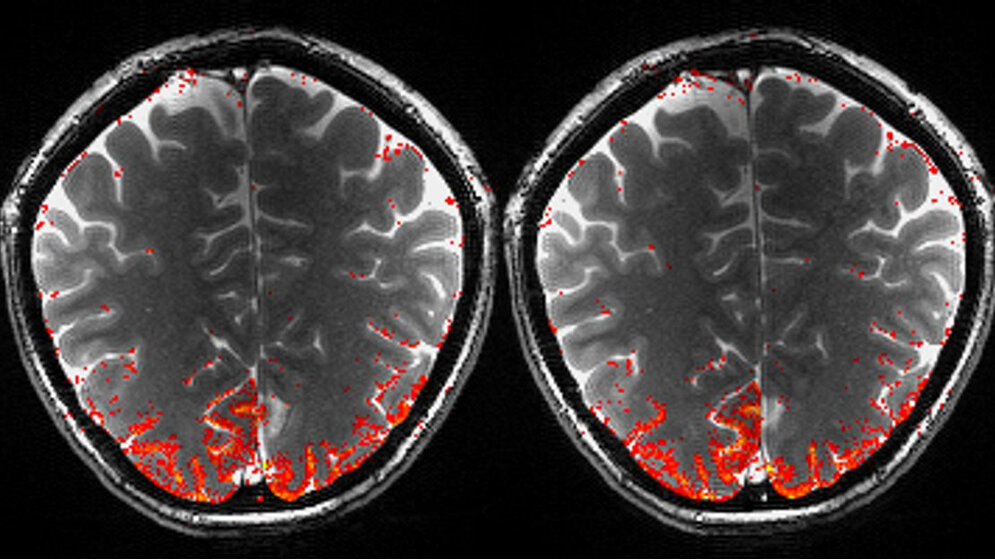

Die Magnetresonanztomographie ist demgegenüber ein nicht invasives Verfahren mit einer sehr hohen räumlichen Auflösung im Millimeter-Bereich und der Möglichkeit, das gesamte Gehirn im Menschen oder Tier zu erfassen. Die Magnetresonanz wird oft als ein alternatives Verfahren zu invasiven Methoden dargestellt, allerdings kann sie im Gegensatz zu elektrophysiologischen Ableitungen neuronale Aktivität bislang nicht direkt messen. Man behilft sich in der Forschung daher mit einem methodischen Umweg: Die Magnetresonanztomographie kann im Gehirn lokale Veränderungen des Sauerstoffgehalts im Blut sichtbar machen, was wiederum durch die Aktivität der Nerven beeinflusst wird.

„Diese sogenannte neurovaskuläre Kopplung ist derzeit noch nicht vollständig verstanden“, sagt Scheffler: „Ein Rückschluss auf die zugrundeliegende neuronale Aktivität des Gehirns aufgrund funktioneller MRT-Daten ist daher sehr schwierig wenn nicht unmöglich.“ Das neu bewilligte Koselleck- Projekt hat daher zum Ziel, die Beziehungen zwischen vaskulären und neuronalen Signalen besser zu verstehen. In diesem Projekt werden neuartige Magnetresonanz-Methoden untersucht mit dem Ziel, detailliertere Informationen über die zugrundeliegenden neuronalen Aktivitäten zu erlangen. Dazu ist es wichtig, die genaue Anatomie des neuronalen Gefäßsystems zu kennen, welches durch tierexperimentelle Ansätze mit hochauflösendem MicroCT gemessen wird. Insgesamt will das bewilligte Koselleck-Projekt also dazu beitragen, ein genaueres Bild der neuronalen Interaktionen des gesamten Gehirns als System zu erlangen.